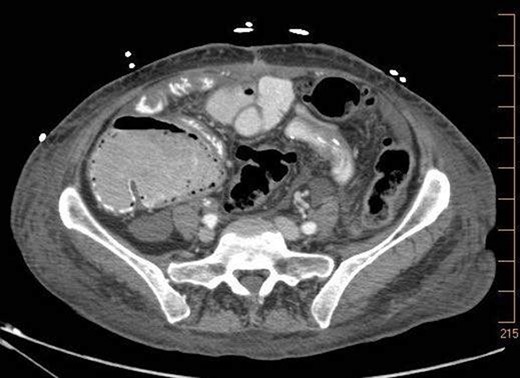

A 57-year-old non-toxic appearing female with a medical history of diverticulosis and malnutrition, and a surgical history significant for small bowel obstruction due to jejunal lymphangioma status post exploratory laparotomy and resection of bowel (2.2018). This patient presents with epigastric pain ×2 days with radiation to left upper quadrant and nausea with emesis, concerning for obstruction. In the Emergency Department, the patient was non-toxic appearing, hemodynamically stable, with no leukocytosis (7.4), or elevated lactic acid (1.2). Imaging, XR (Fig. 1) and CTAP (Fig. 2), demonstrating SBO with free air concern for perforated viscus. The concern for free air on imaging, in the setting of abdominal pain with symptoms of obstruction, mandated an operative intervention. On 7.5.18 the patient underwent exploratory laparotomy and was found to have emphysema of proximal jejunum, and underwent 125 cm resection of jejunum (Figs 3 and 4). Pathology of the specimen demonstrated multiple air filled cystic serosal nodules consistent with PCI (Figs 3 and 4, Supplementary Fig. S7).

Multiple air filled cystic serosal nodules consistent with pneumatosis cystoides intestinalis.